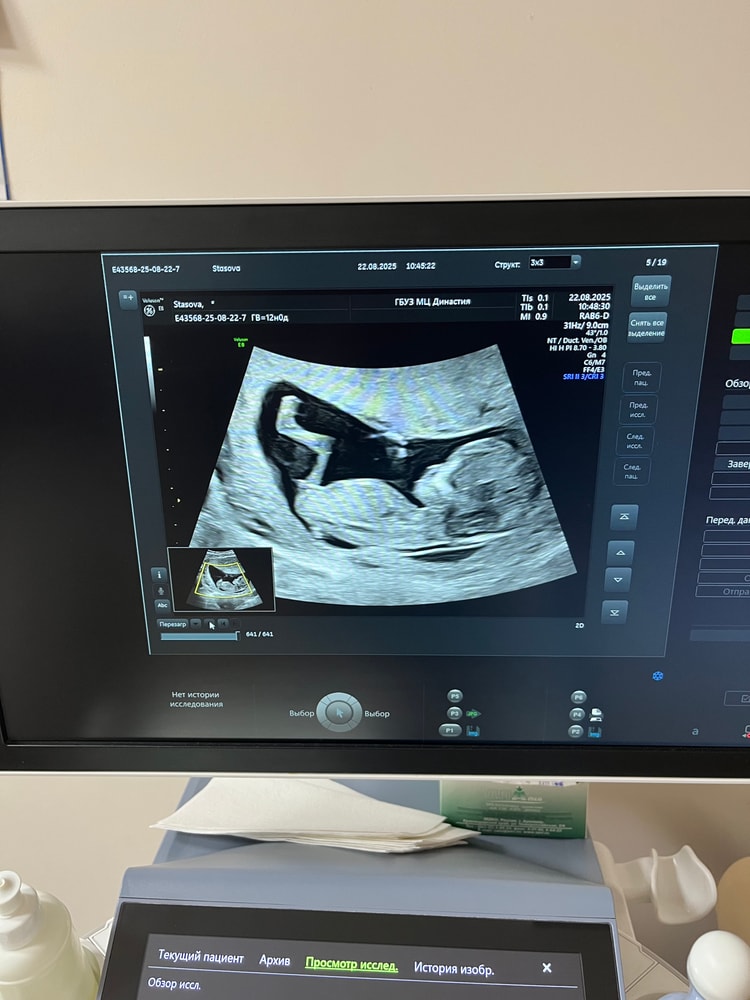

Мама двоих (11 лет, 6 лет), жду девочку, 17 неделя

Девочки, кто понимает по фото, как думаете это всё-таки девочка? На узи ничего не сказали, а я всё еще переживаю что анализ крови мог быть ошибочным.

А у нас так же было. Прям точь в точь. У меня сын. Жаль что фото остались на разбитом телефоне и их не восстановить( а у дочери вообще бугорок этот был мизерным, почти не видно). Но это у нас так. Вообще, если вниз смотрит, то скорей всего девочка

Девочка. Параллельно позвоночнику. Без угла

Это девочка, без вариантов 👌